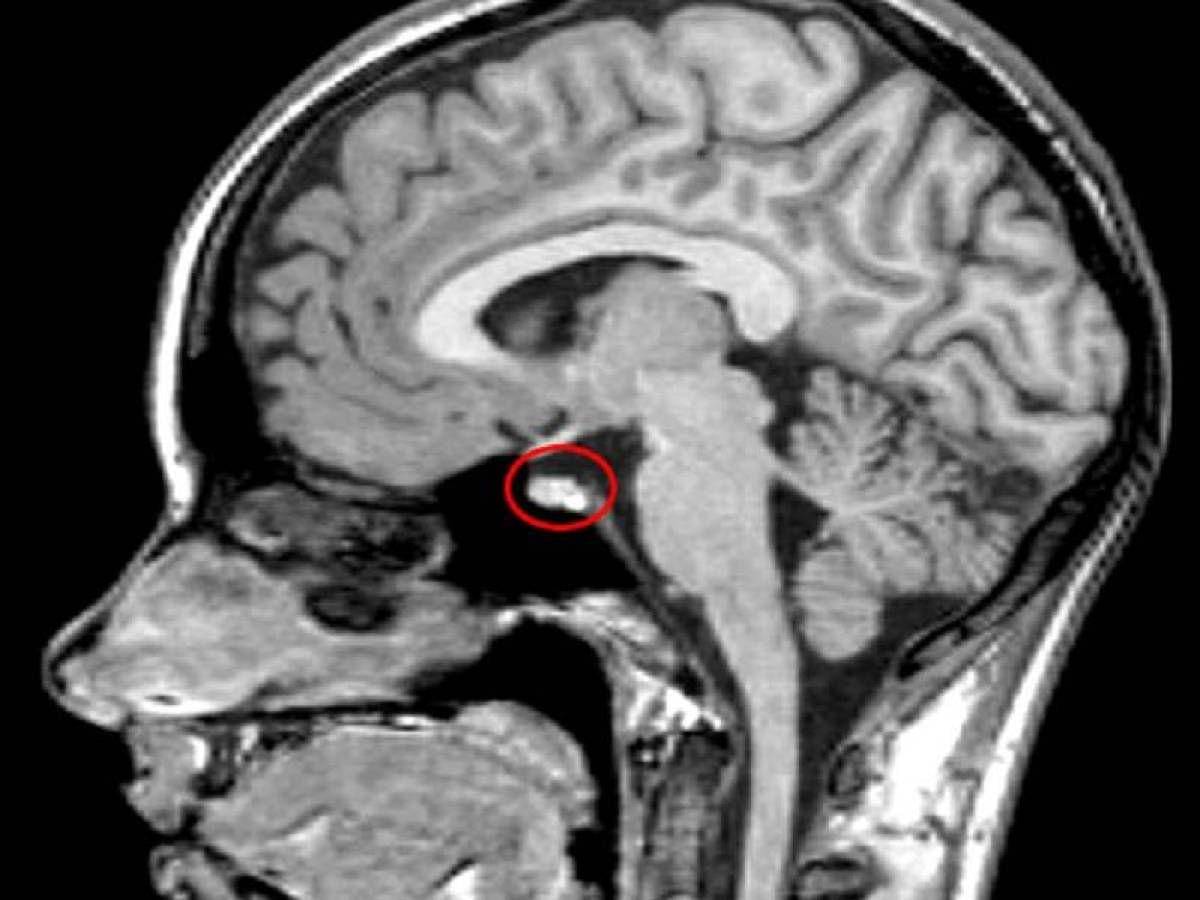

Pada Desember 1930, ketika Rainer berusia 31 tahun, seorang ahli bedah otak menganestesi Rainer secara lokal dan menaruh suatu alat ke dalam hidungnya, untuk memperoleh akses ke kelenjar pituitary-nya, sebuah struktur kecil yang berlokasi di daerah yang susah dijangkau dalam otak.

Ahli bedah tersebut menemukan eosinophilic adenoma, sebuah tumor jinak yang menekan bagian pituitary tersebut. Prosedur ini secara drastis memperlambat pertumbuhan Rainer, tapi telah banyak kerusakan tubuh yang sudah telanjur terjadi.